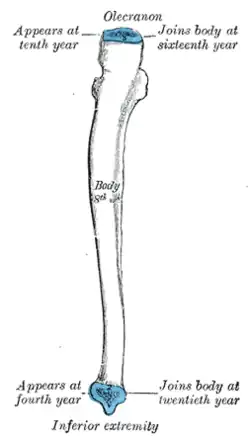

Development

The ulna is ossified from three centers: one each for the body, the wrist end, and the elbow end, near the top of the olecranon. Ossification begins near the middle of the body of the ulna, about the eighth week of fetal life, and soon extends through the greater part of the bone.

At birth, the ends are cartilaginous. About the fourth year or so, a center appears in the middle of the head, and soon extends into the ulnar styloid process. About the tenth year, a center appears in the olecranon near its extremity, the chief part of this process being formed by an upward extension of the body. The upper epiphysis joins the body about the sixteenth, the lower about the twentieth year.